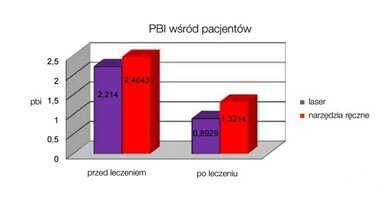

Laser Er: i Nd:YAG są obecnie narzędziem z wyboru w specjalistycznej terapii chorób przyzębia. Skutecznie redukują krwawienie (BoP) oraz głębokość kieszeni (Pd) w relatywnie krótszym czasie w porównaniu do konwencjonalnych metod leczenia. Inną zaletą jest większy dostęp światła lasera niż w przypadku narzędzi ręcznych, szczególnie w miejscach trudnodostępnych, jak np. głębokie wąskie kieszenie, furkacje czy bruzdy.